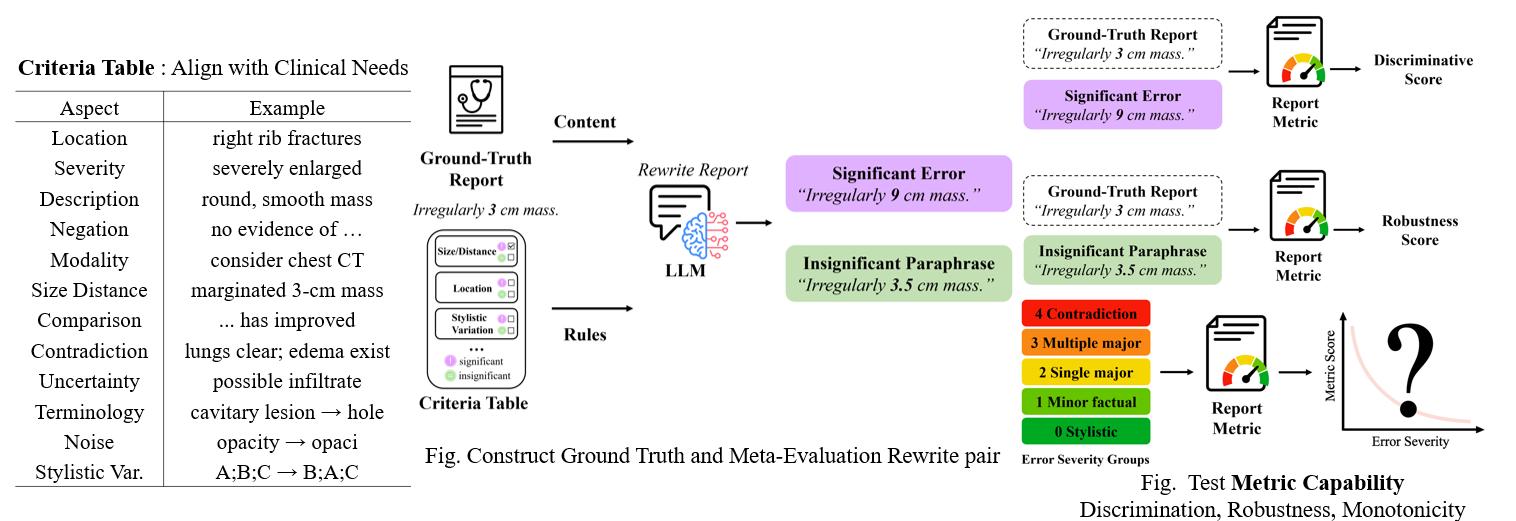

Jun Li, Che Liu, Wenjia Bai, Rossella Arcucci, Cosmin I. Bercea, Julia A. Schnabel.

[paper]

[project]

[huggingface]